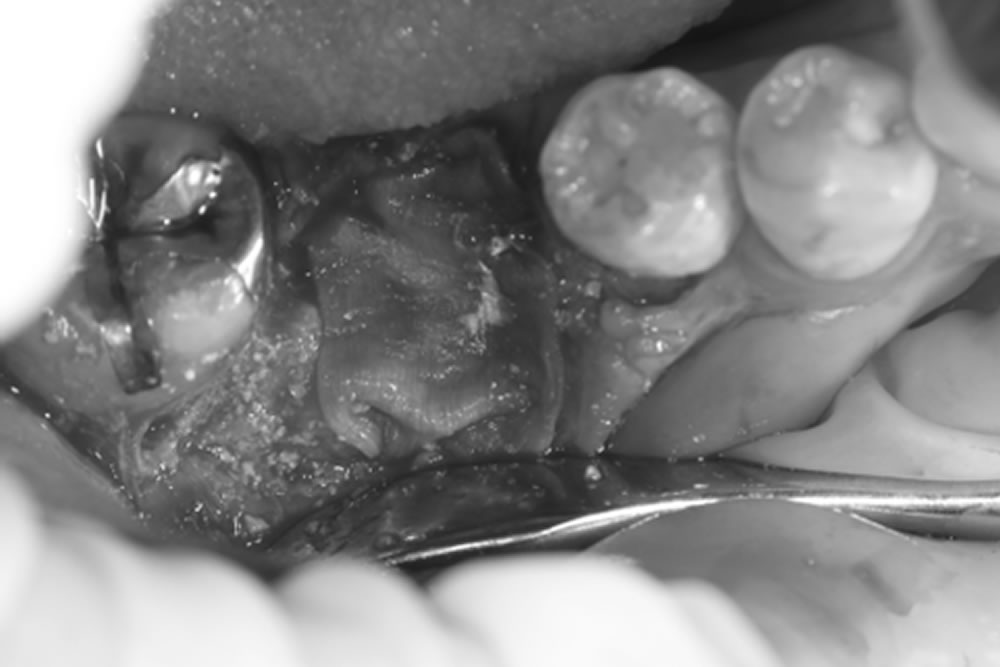

- 11.5 ④骨造成の実施

- 11.6 ⑤患部の保護

GBR(骨再生誘導法)

GBR法(骨誘導再生法)は、骨の厚みや高さが不足している場合に行う骨造成法です。骨が不足している部分の歯茎を切開し、自家骨や骨補填材を入れ、メンブレンという保護膜で覆って骨の再生を促進します。